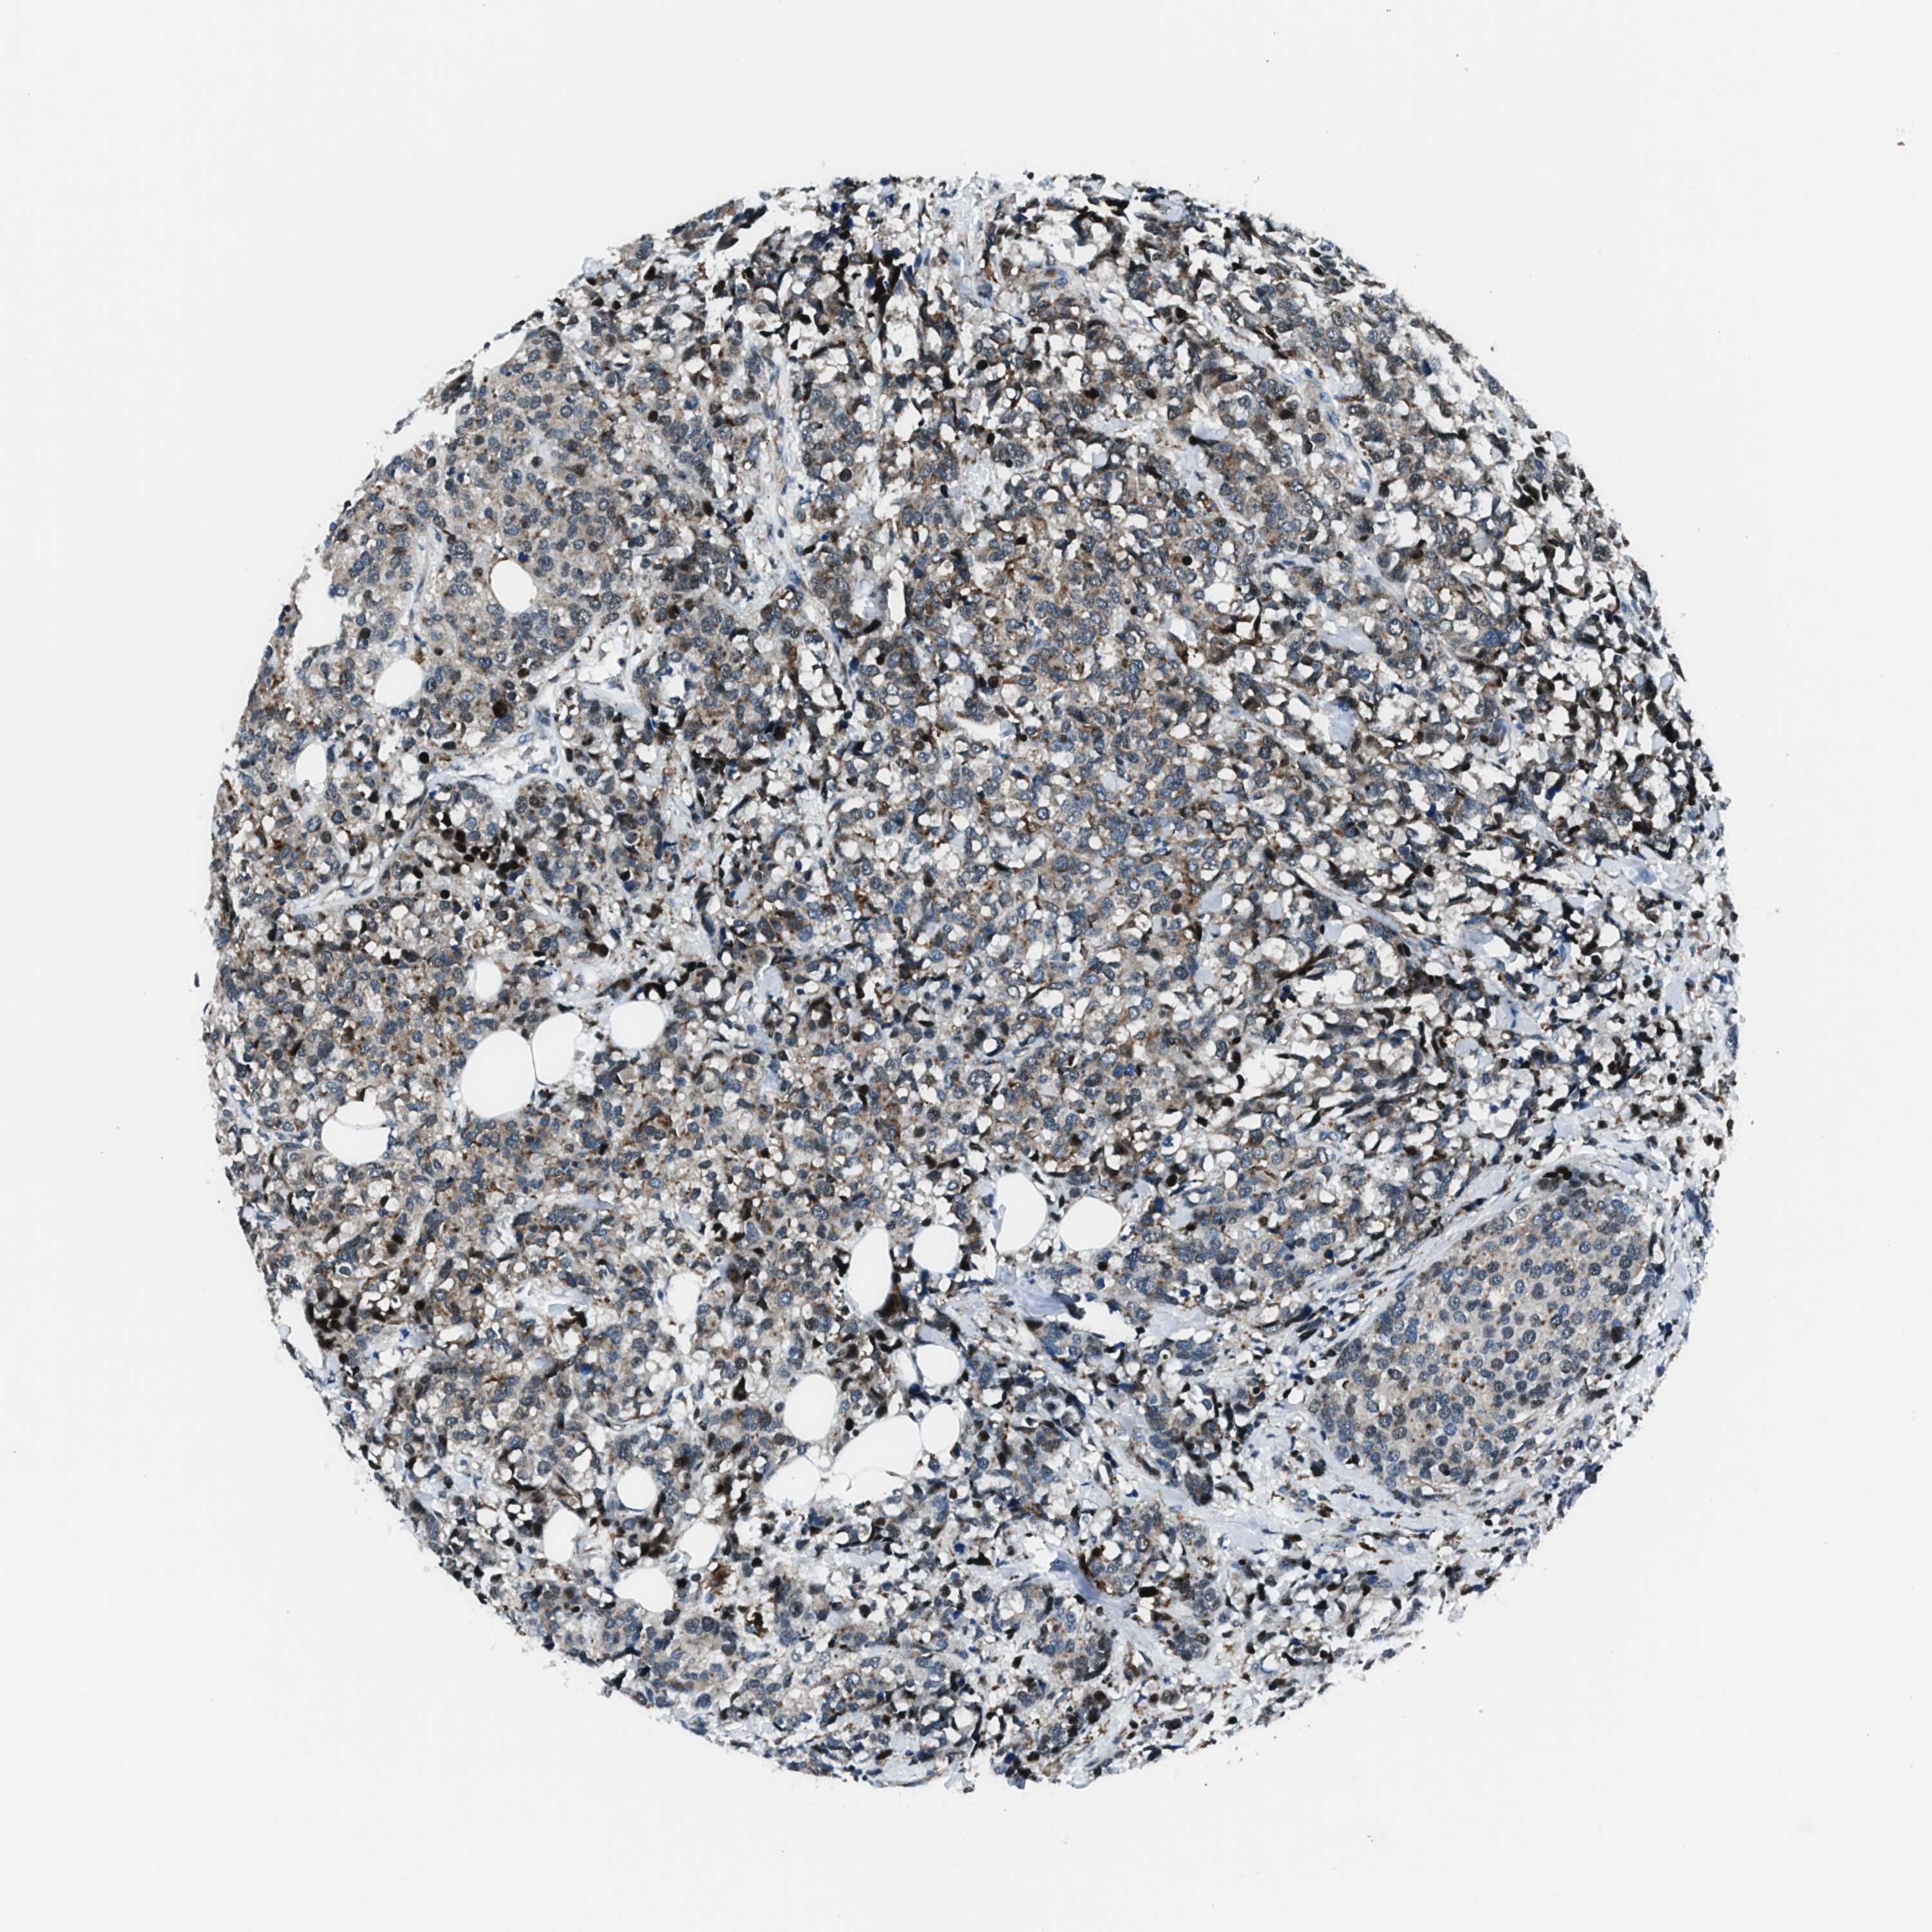

BRCA TCGA BRCA VALIDATION PROTEIN EXPRESSION